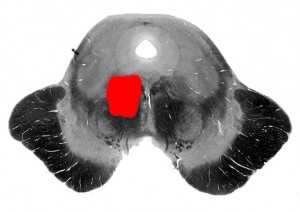

Синдром Клода характеризуется параличом глазодвигательного нерва на стороне очага поражения и мозжечковыми явлениями (нарушение координации и содружественного характера движений), а также понижением тонуса мышц на противоположной стороне. Иногда при этом наблюдается дизартрия и расстройство глотания.Синдром Клода — при поражении глазодвигательного нерва и заднего отдела красного ядра (нижний синдром красного ядра).

Один из педункулярных альтернирующих синдромов ствола мозга. Относится к синдромам покрышки среднего мозга. Возникает при поражении корешка или ядер глазодвигательного нерва, дорсальной части красного ядра (возможны варианты с вовлечением волокон верхней мозжечковой ножки от перекреста Вернекинка до красного ядра, или волокон руброспинального пути), иногда - ядра подъязычного нерва (XII пара).

Нижний синдром красного ядра (синдром Клода — Луае)

Синдром впервые описан французским неврологом Н. Claude в 1912 г. Патологический очаг располагается в покрышке среднего мозга. Он повреждает нижнюю крупноклеточную часть красного ядра с проходящим через нее корешком III черепного нерва. Ведущим этиологическим фактором синдрома являются сосудистые расстройства в бассейне рубральных ветвей задней мозговой артерии.

1. Ипсилатерально определяется симптомокомплекс поражения III черепного нерва.

2. Контралатерально выявляется мозжечковая гемиатаксия.

Синдром красного ядра нижний Клода

Синдром красного ядра нижний Клода Альтернирующий синдром (см.) при локализации патологического очага в покрышке среднего мозга, обусловленный поражением нижней части красного ядра, через которую проходит корешок III нерва, а также денто-рубральных связей, проходящих через верхнюю ножку мозжечка. На стороне патологического процесса - признаки поражения глазодвигательного нерва (птоз верхнего века, расширение зрачка, расходящееся косоглазие), а на противоположной стороне - интенционное дрожание (см.), гемиатаксия, мышечная гипотония. Описал в 1912 г. французский невропатолог Н. Claude.